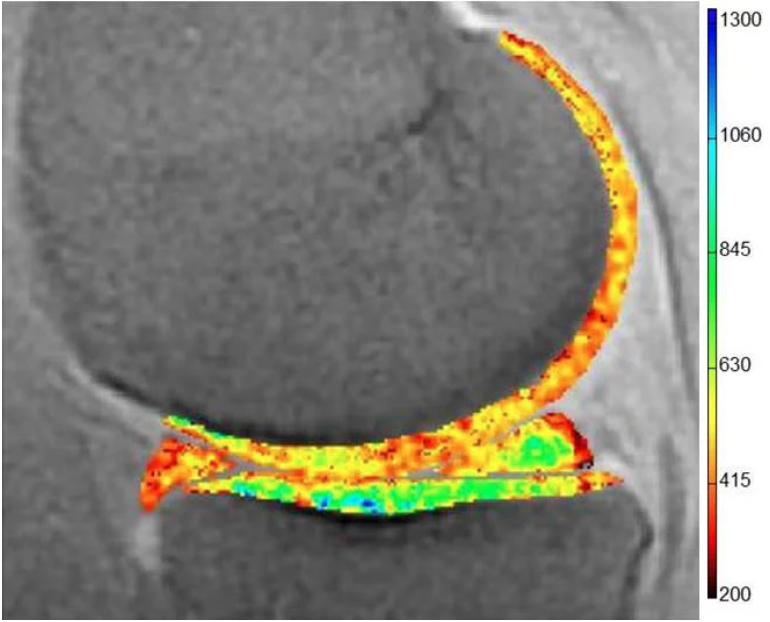

dGEMRIC assessment of the medial tibiofemoral compartment: the superficial and deep zones of cartilage demonstrating a color spectrum from orange to red exhibit low dGEMRIC indices (representing low proteoglycan content within the cartilage matrix). The zones of cartilage displaying a color spectrum from green to blue exhinit high dGEMRIC indices (representing areas of high proteoglycan content).